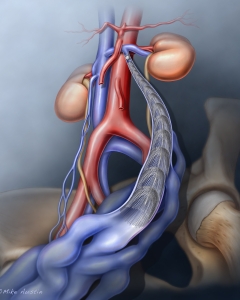

Internal Art Medical Illustration

Blending Art, Anatomy and Science for Creative Visuals

Welcome to my Patient and Professional Marketing page, where I harness the power of anatomical illustrations to educate and empower both patients and medical professionals. My unique approach combines artistry and education to convey complex surgical procedures and the utilization of medical devices in an easily understandable manner.